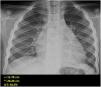

The World Health Organization defines the multisystem inflammatory syndrome in children (MIS-C) as a new syndrome reported in patients aged <19 years old who have a history of exposure to SARS-CoV-2. The onset of this syndrome is characterized by persistent fever that is associated with lethargy, abdominal pain, vomiting and/or diarrhea, and, less frequently, rash and conjunctivitis. The course and severity of the signs and symptoms vary; in some children, MIS-C worsens rapidly and can lead to hypotension, cariogenic shock, or even damage to multiple organs. The characteristic laboratory findings are elevated markers of inflammation and heart dysfunction. The most common radiological findings are cardiomegaly, pleural effusion, signs of heart failure, ascites, and inflammatory changes in the right iliac fossa. In the context of the current COVID-19 pandemic, radiologists need to know the clinical, laboratory, and radiological characteristics of this syndrome to ensure the correct diagnosis.

El síndrome inflamatorio multisistémico pediátrico vinculado a la COVID-19 (SIM-PedS) es, según la Organización Mundial de la Salud, un nuevo síndrome descrito en pacientes menores de 19 años con historia previa de exposición a SARS-CoV-2. La presentación inicial de este síndrome se caracteriza por fiebre persistente que asocia debilidad, dolor abdominal, vómitos y/o diarrea. Menos frecuentemente los pacientes pueden presentar también erupción cutánea y conjuntivitis. El cuadro clínico tiene expresividad y evolución variables, por lo que algunos pacientes pediátricos afectados pueden empeorar rápidamente, desarrollando desde hipotensión y shock cardiogénico a daño multiorgánico. Los hallazgos analíticos característicos del síndrome consisten en elevación de marcadores inflamatorios y disfunción cardíaca. Los hallazgos radiológicos más frecuentes son cardiomegalia, derrame pleural, signos de insuficiencia cardíaca, ascitis y cambios inflamatorios en la fosa ilíaca derecha. En la pandemia actual por COVID-19 es necesario que el radiólogo conozca las características clínico-analíticas y radiológicas de este síndrome para realizar un correcto diagnóstico.